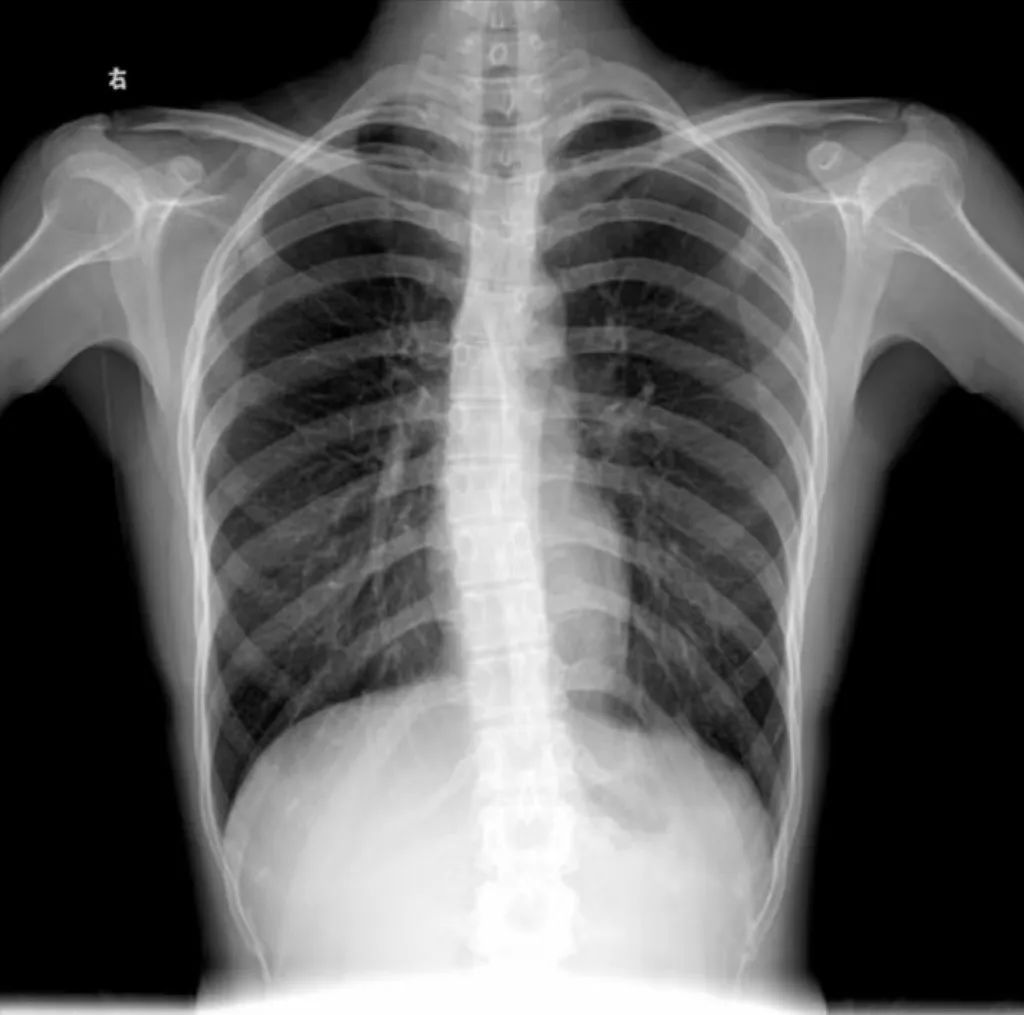

现在喜欢盘腿而坐的年轻人当中,十有八九都有脊柱侧弯的问题。

这类拉伸器虽然被称为“脊椎拉伸器”,但大多数并没有相应的医学资质,不能作为专业的矫正设备。

如果使用不当,不仅可能引发腰痛,还可能加重脊柱弯曲。

当您出现脊柱问题时,建议您寻求专业医务人员的帮助。